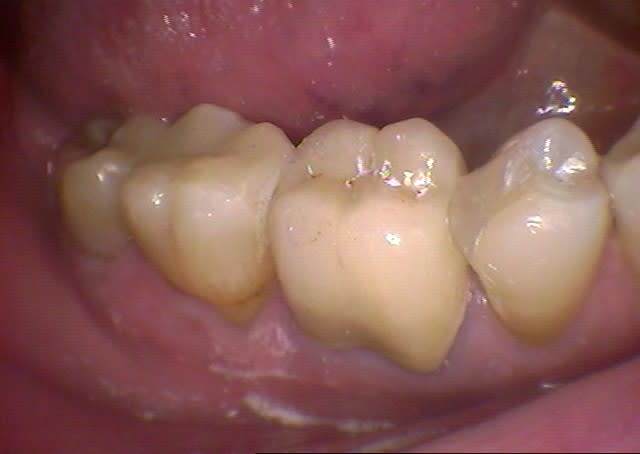

Je viens de recevoir mon cerec 4.02 et je n'ai que 2 jours de pratique, je vous livre mon avis en tant que nouvel utilisateur sans comparaison possible avec les versions antérieures:

Le logiciel me parait assez complet, bien structuré et interactif.

L'empreinte optique ne pose aucun problème après des gingivoplasties dans la même séance au CO².

la FAO est très rapide.

La précision est bluffante.

Mais une machine reste une machine...

Pour preuve, mes 2 premières couronnes ont du être refaites car,elles se sont docilement mise en contact avec leurs antagonistes en attente de prothèses en prenant des formes globuleuses, il fallait naturellement réaliser des retouches correctives sur le logiciel mais encore fallait-il le savoir!(leçon n°1)

J'ai réalisé plusieurs onlays dont 2 simultanés sans problème mais j'ai eu des difficultés à placer mon premier onlay dans une cavité où j'avais laissé volontairement des contre dépouilles devant être comblées par le composite de collage, il aurait mieux valu ne pas hésiter à tailler d'avantage (leçon n°2)

Les avantages sont indéniables et connus mais j'apprécie surtout le fait de pouvoir tailler sans soucis de casse lors de parois fines résiduelles puisqu'elles sont immédiatement consolidées par le collage des céramiques ainsi que de ne plus être limité par le volume des piliers de couronnes, ce qui change radicalement mes critères de taille.

Naturellement il me reste à suivre la courbe d'apprentissage et vos avis sont toujours les bienvenus.

Quelques illustrations: